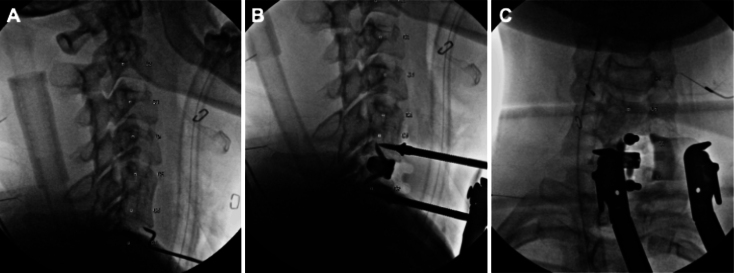

Observations: The authors present the case of a woman in her mid-30s at 24 weeks of gestation, conceived via in vitro fertilization, who developed progressively worsening left C7 radiculopathy refractory to conservative therapies. After comprehensive multidisciplinary evaluation, she underwent successful anterior cervical discectomy and fusion with placement of a stand-alone interbody cage. Perioperative planning incorporated anesthetic modifications, fetal monitoring strategies, and minimization of radiation exposure. The patient experienced immediate postoperative relief, rapid functional recovery, and an uncomplicated pregnancy course.